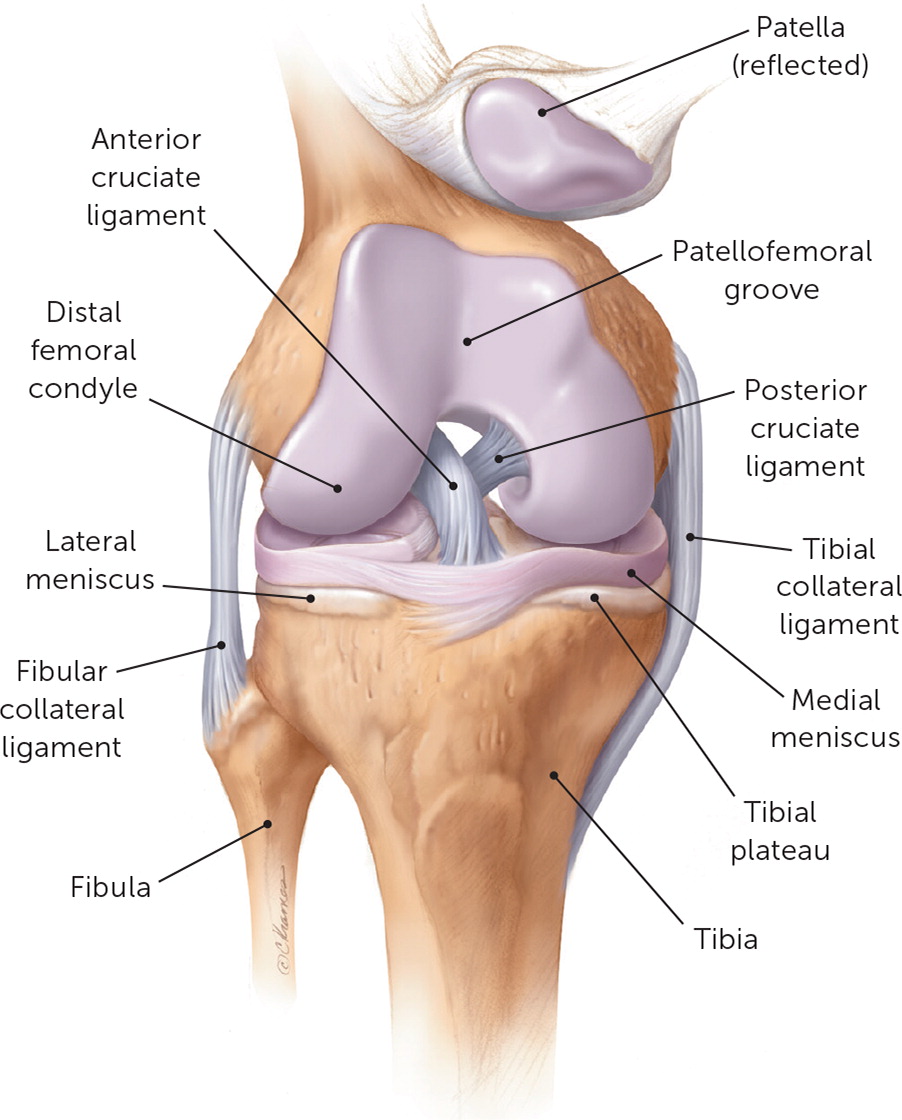

Анатомические изображения менисков и коленного сустава

Раздел: Иллюстрированные советы